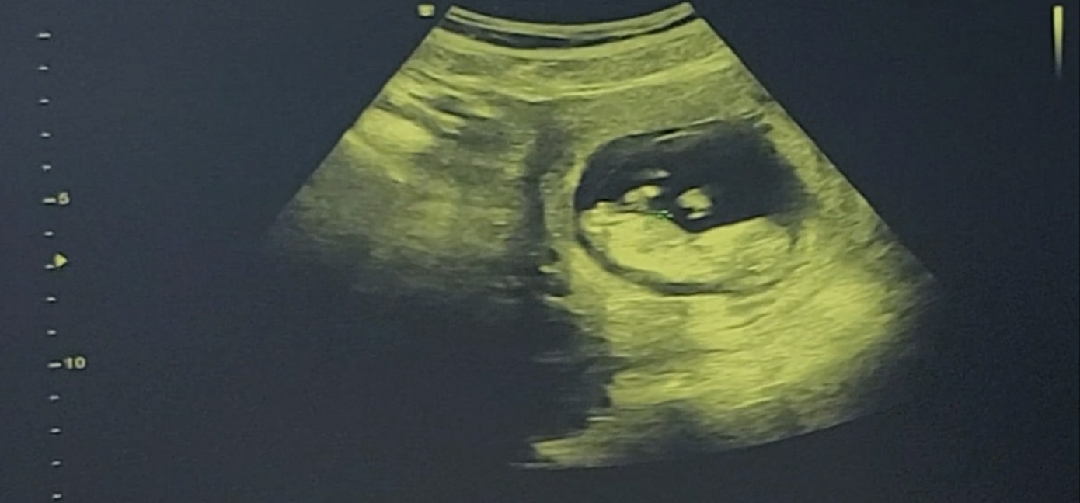

11주차 5일인데 성별 알수있을까요 ㅎㅎ

다리 밑에 제 눈에는 보이는 것 같은데 ㅎㅎㅎ 각도법으로 알 수 있을까요 ㅎ 한 달 뒤에 정기검진하러 오라하길래 궁금해 죽겠네요 ㅎㅎ